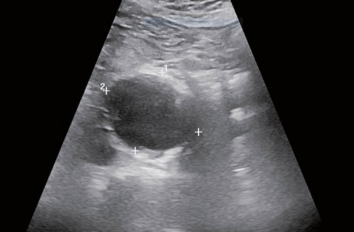

Vaskulitiden sind in Ätiologie und Manifestation sehr mannigfaltig. Als Arteriitiden, also Grossgefässvaskulitiden, gelten die Riesenzellarteriitis und die Takayasu-Arteriitis,…